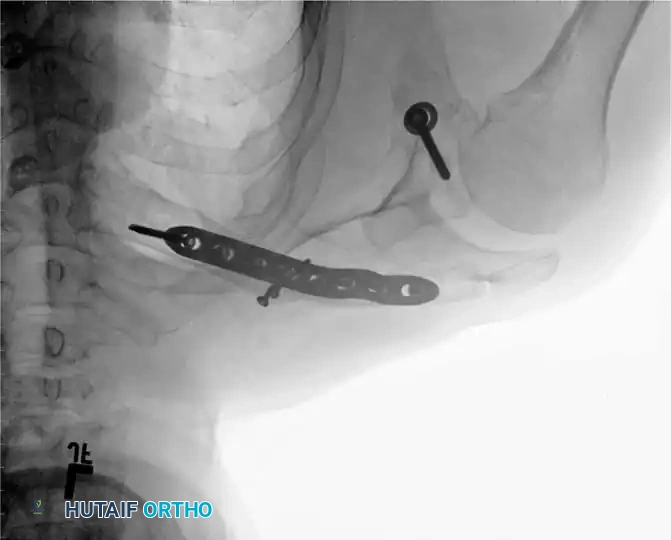

Fluoroscopic AP view demonstrating the use of a threaded pin as a joystick in the humeral head to achieve and maintain reduction.

Fluoroscopic lateral view confirming the central placement of the guidewire within the humeral canal.